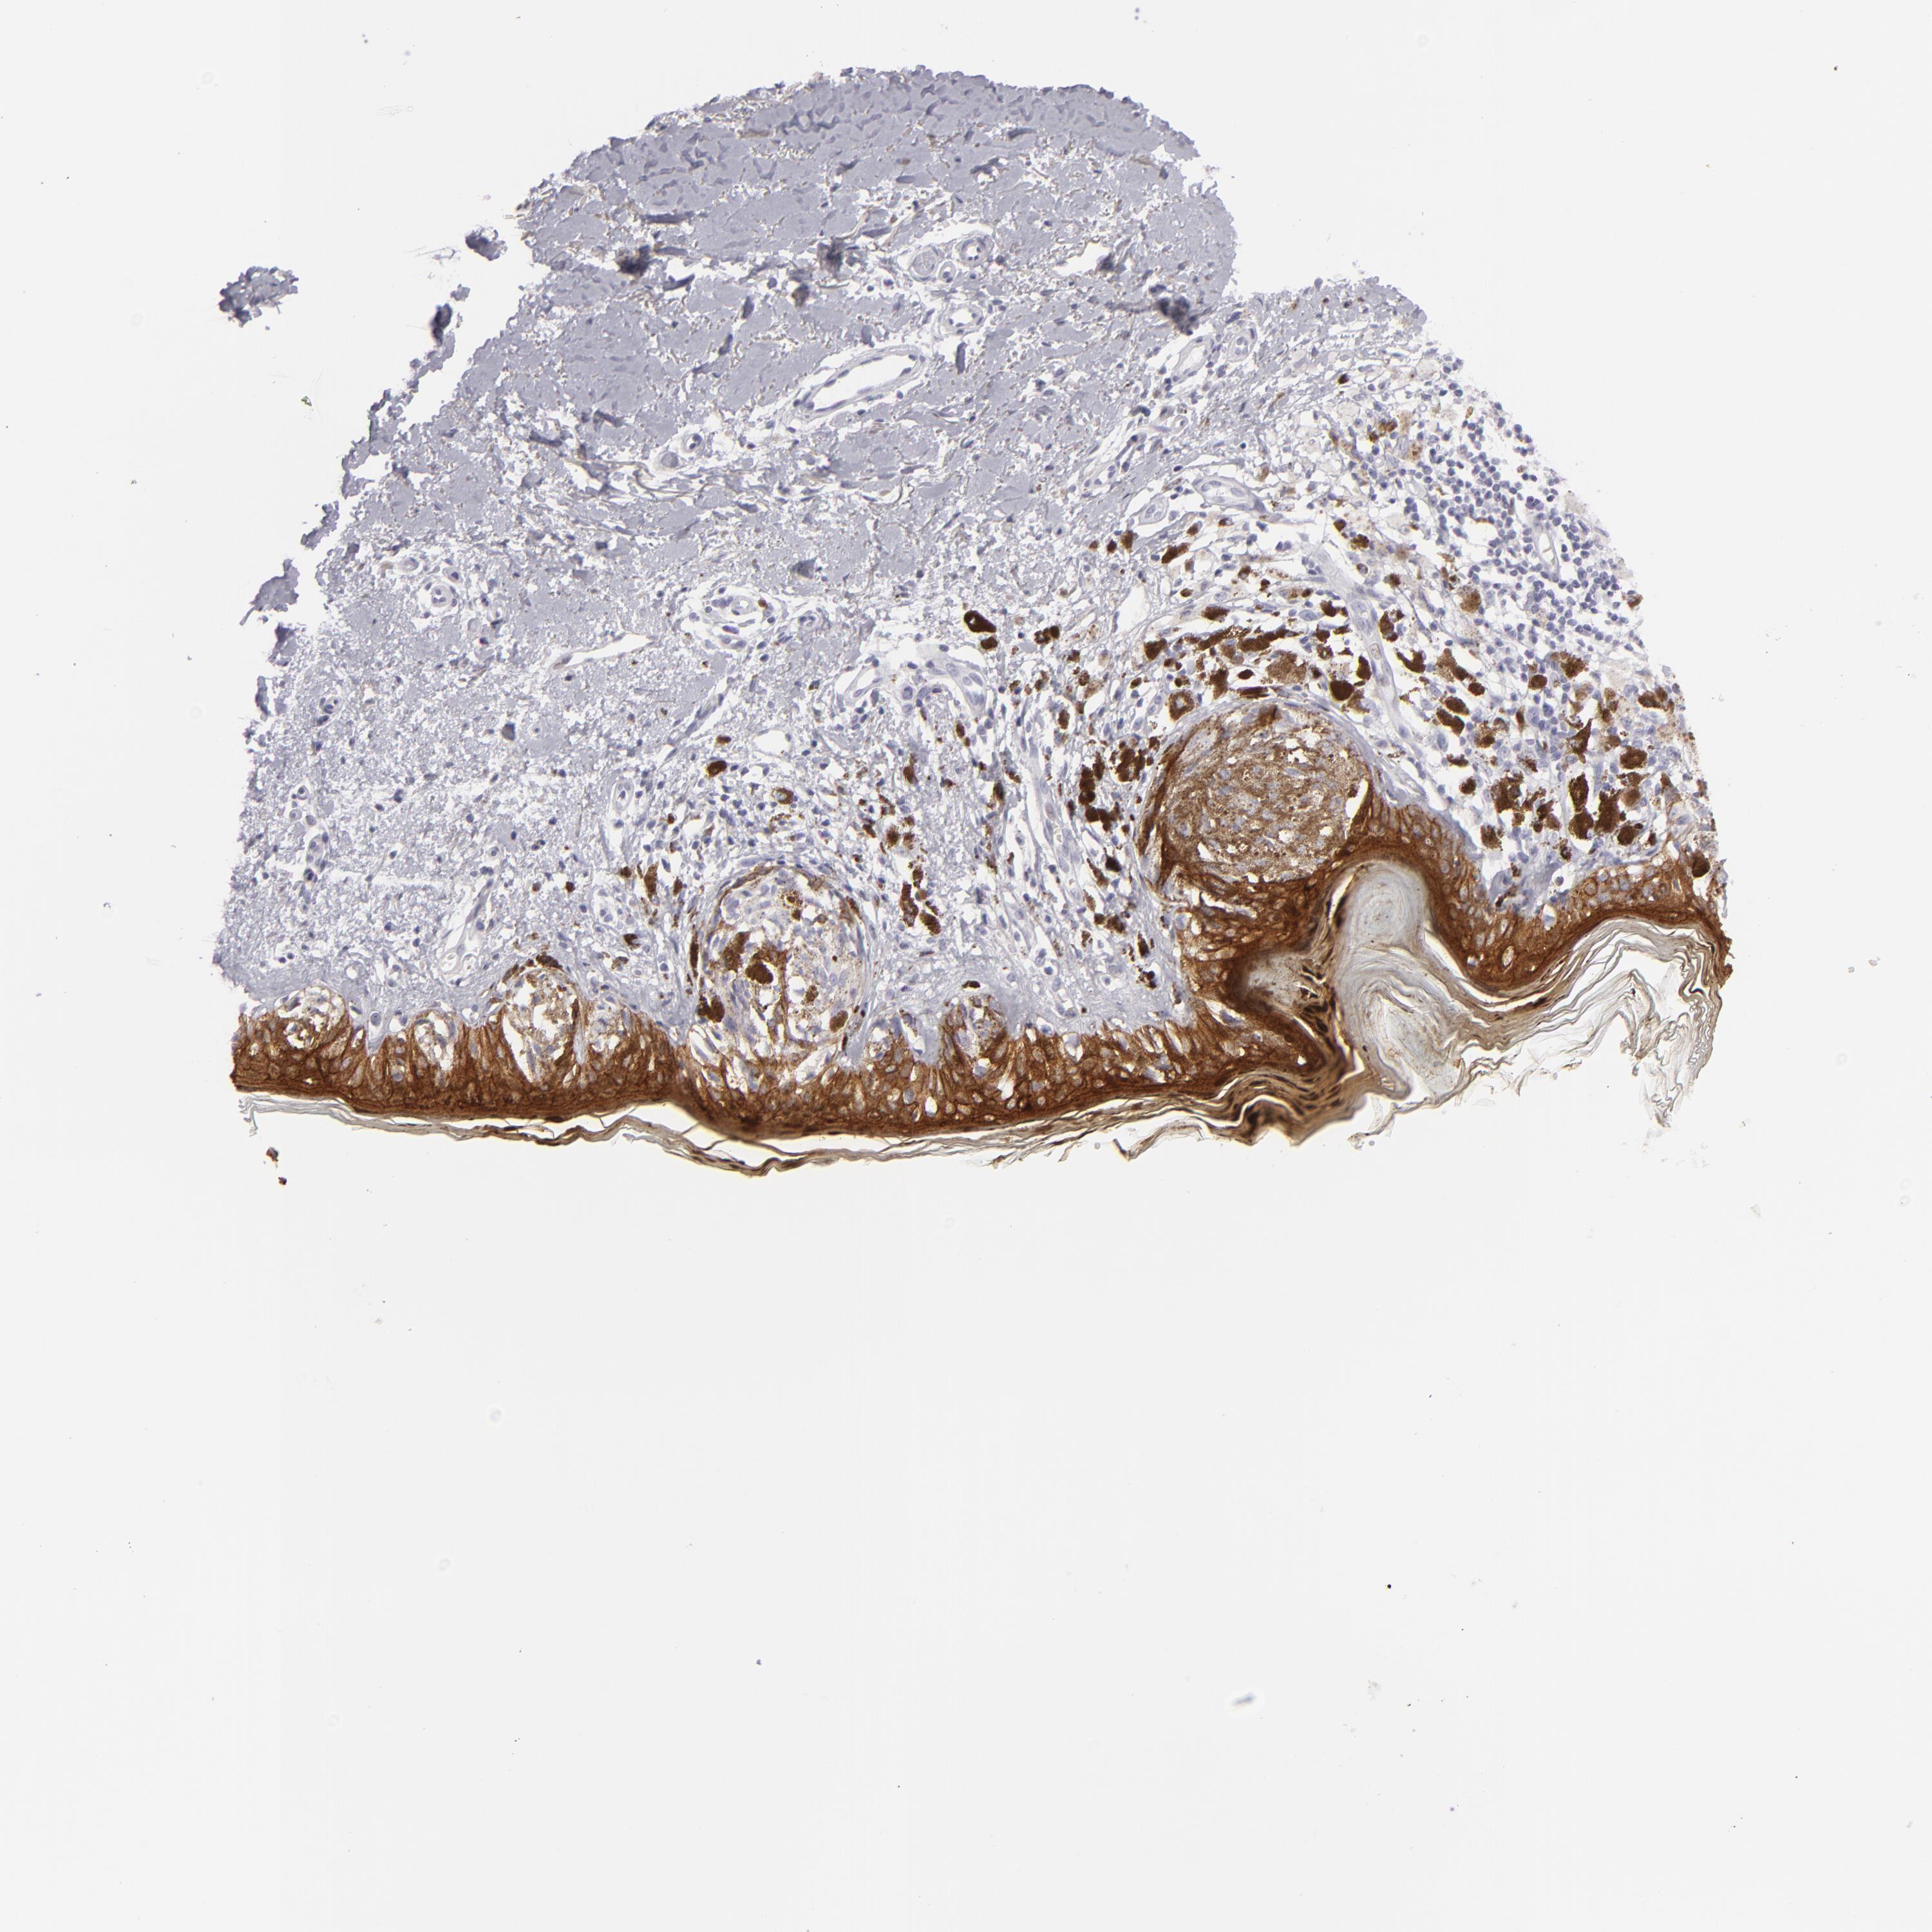

MELANOMA - Protein expressioni

A mouse-over function shows sample information and annotation data. Click on an image to view it in a full screen mode. Samples can be filtered based on level of antibody staining by selecting one or several of the following categories: high, medium, low and not detected. The assay and annotation is described here.

Note that samples used for immunohistochemistry by the Human Protein Atlas do not correspond to samples in the TCGA dataset.

Antibody stainingi

Antibody staining in the annotated cell types in the current human tissue is reported as not detected, low, medium, or high, based on conventional immunohistochemistry profiling in selected tissues. This score is based on the combination of the staining intensity and fraction of stained cells.

Each image is clickable and will lead to virtual microscopy that enables deeper exploration of all samples and also displays staining intensity scores, fraction scores and subcellular localization as well as patient and tissue information for each sample.

Antibody HPA032047

Antibody CAB002139

Staining

High

Medium

Low

Not detected

Intensity

Strong

Moderate

Weak

Negative

Quantity

>75%

75%-25%

<25%

None

Location

Nuclear

Cytoplasmic/membranous

Cytoplasmic/membranous,nuclear

Malignant melanoma, NOS

Malignant melanoma, Metastatic site